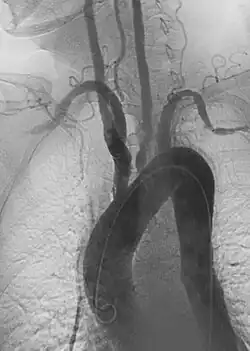

1. Angiography: Sometimes referred to as traditional angiography, catheter angiography or digital subtraction angiography (DSA). A small needle is inserted into a blood vessel, then exchanged for a catheter over a wire. The catheter is directed at the vessel to be studied, and contrast is directly injected to evaluate the lumen under video X-ray. This is an older technique than modern CT angiography or MR angiography, but provides unique advantages. With a catheter in place, provocative maneuvers can be performed such as breath holds or instillation of vasodilators, to evaluate a patient's blood flow dynamically. This can reproduce symptoms and identify functional abnormalities in a vessel that a static CT or MR imaging cannot.[80][81] Angiography provides the basis for all endovascular therapy.

There are several systems for staging PAD, but an often used scale is the revised Rutherford classification.[76][89] Plaque and blood flow can be evaluated using ultrasound, CT angiography, MR angiography, and catheter-based angiography to establish anatomic segments of disease. The severity of ischemia can be evaluated by correlating symptoms and non-invasive physiologic vascular studies including toe pressures, TCPO2, and skin perfusion studies.